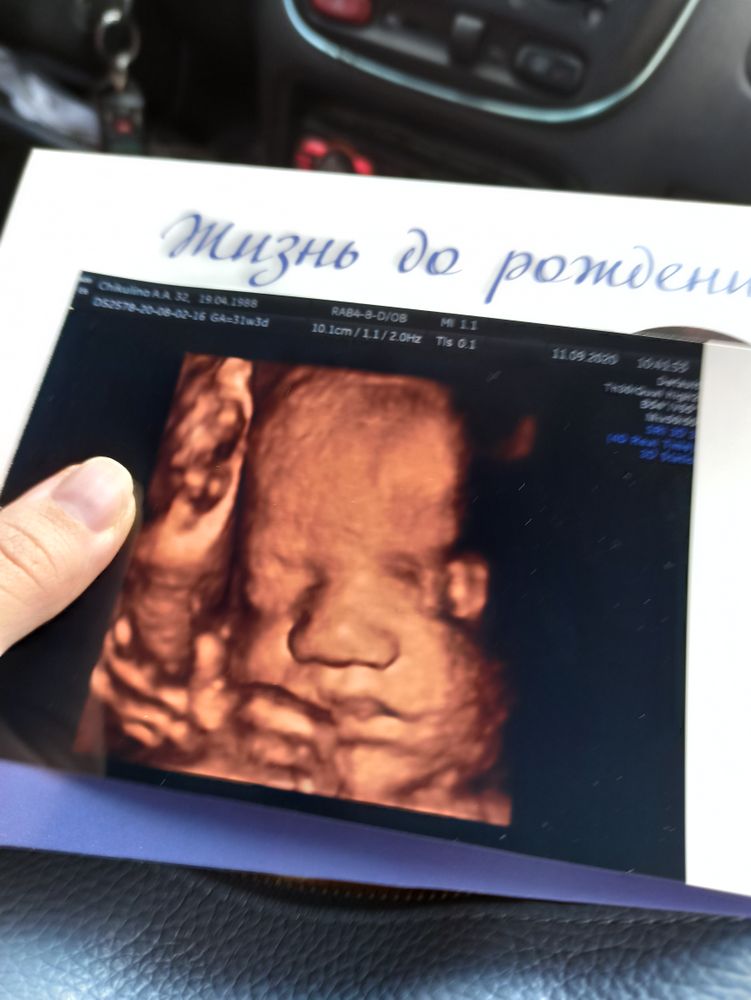

Вот такой пупс)